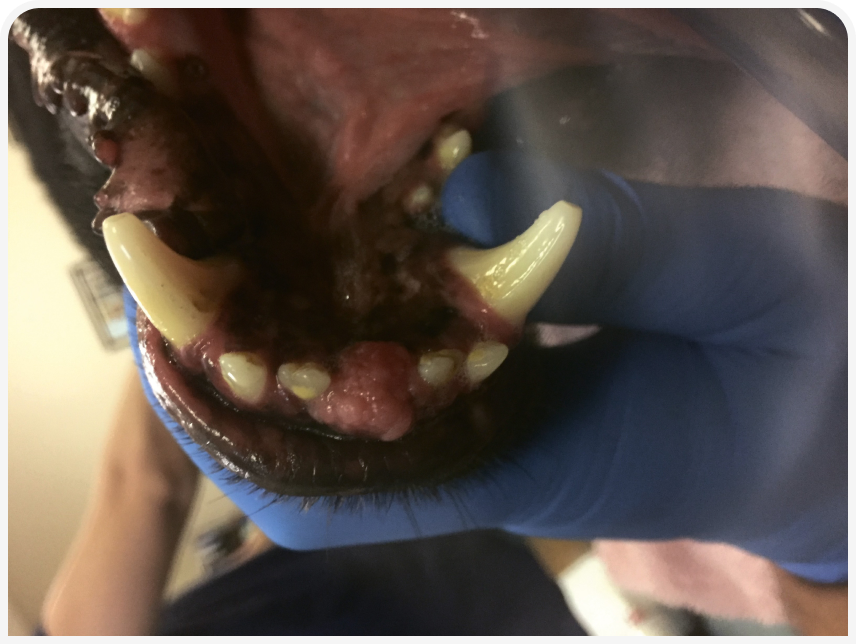

Гиперплазия десен — неопухолевое реактивное воспалительное поражение десен с различными внешними проявлениями (Рисунок 1). Наиболее распространенные причины — гингивит/пародонтит, вызванные скоплением зубного налета, окклюзионная травма, некоторые лекарственные препараты (чаще всего циклоспорин и амлодипин) (2). Форму гиперплазии десен, характеризующуюся незначительной гиперплазией эпителия и преобладанием плотной волокнистой соединительной ткани, называют очаговой фиброзной гиперплазией (2).

Периферическую одонтогенную фиброму (Peripheral Odontogenic Fibroma — POF) также иногда называют фиброматозным эпулисом из периодонтальной связки (Fibromatous Epulis of Periodontal Ligament Origin — FEPLO). Окончательное название для поражения этого типа еще не выбрано (2), поэтому, чтобы не усугублять противоречия, мы будем использовать комбинированную аббревиатуру FEPLO/POF. Клинически оно, как правило, экзофитное, на широком основании, с гладкой текстурой и неповрежденным эпителием, но может по виду напоминать цветную капусту (Рисунок 2).